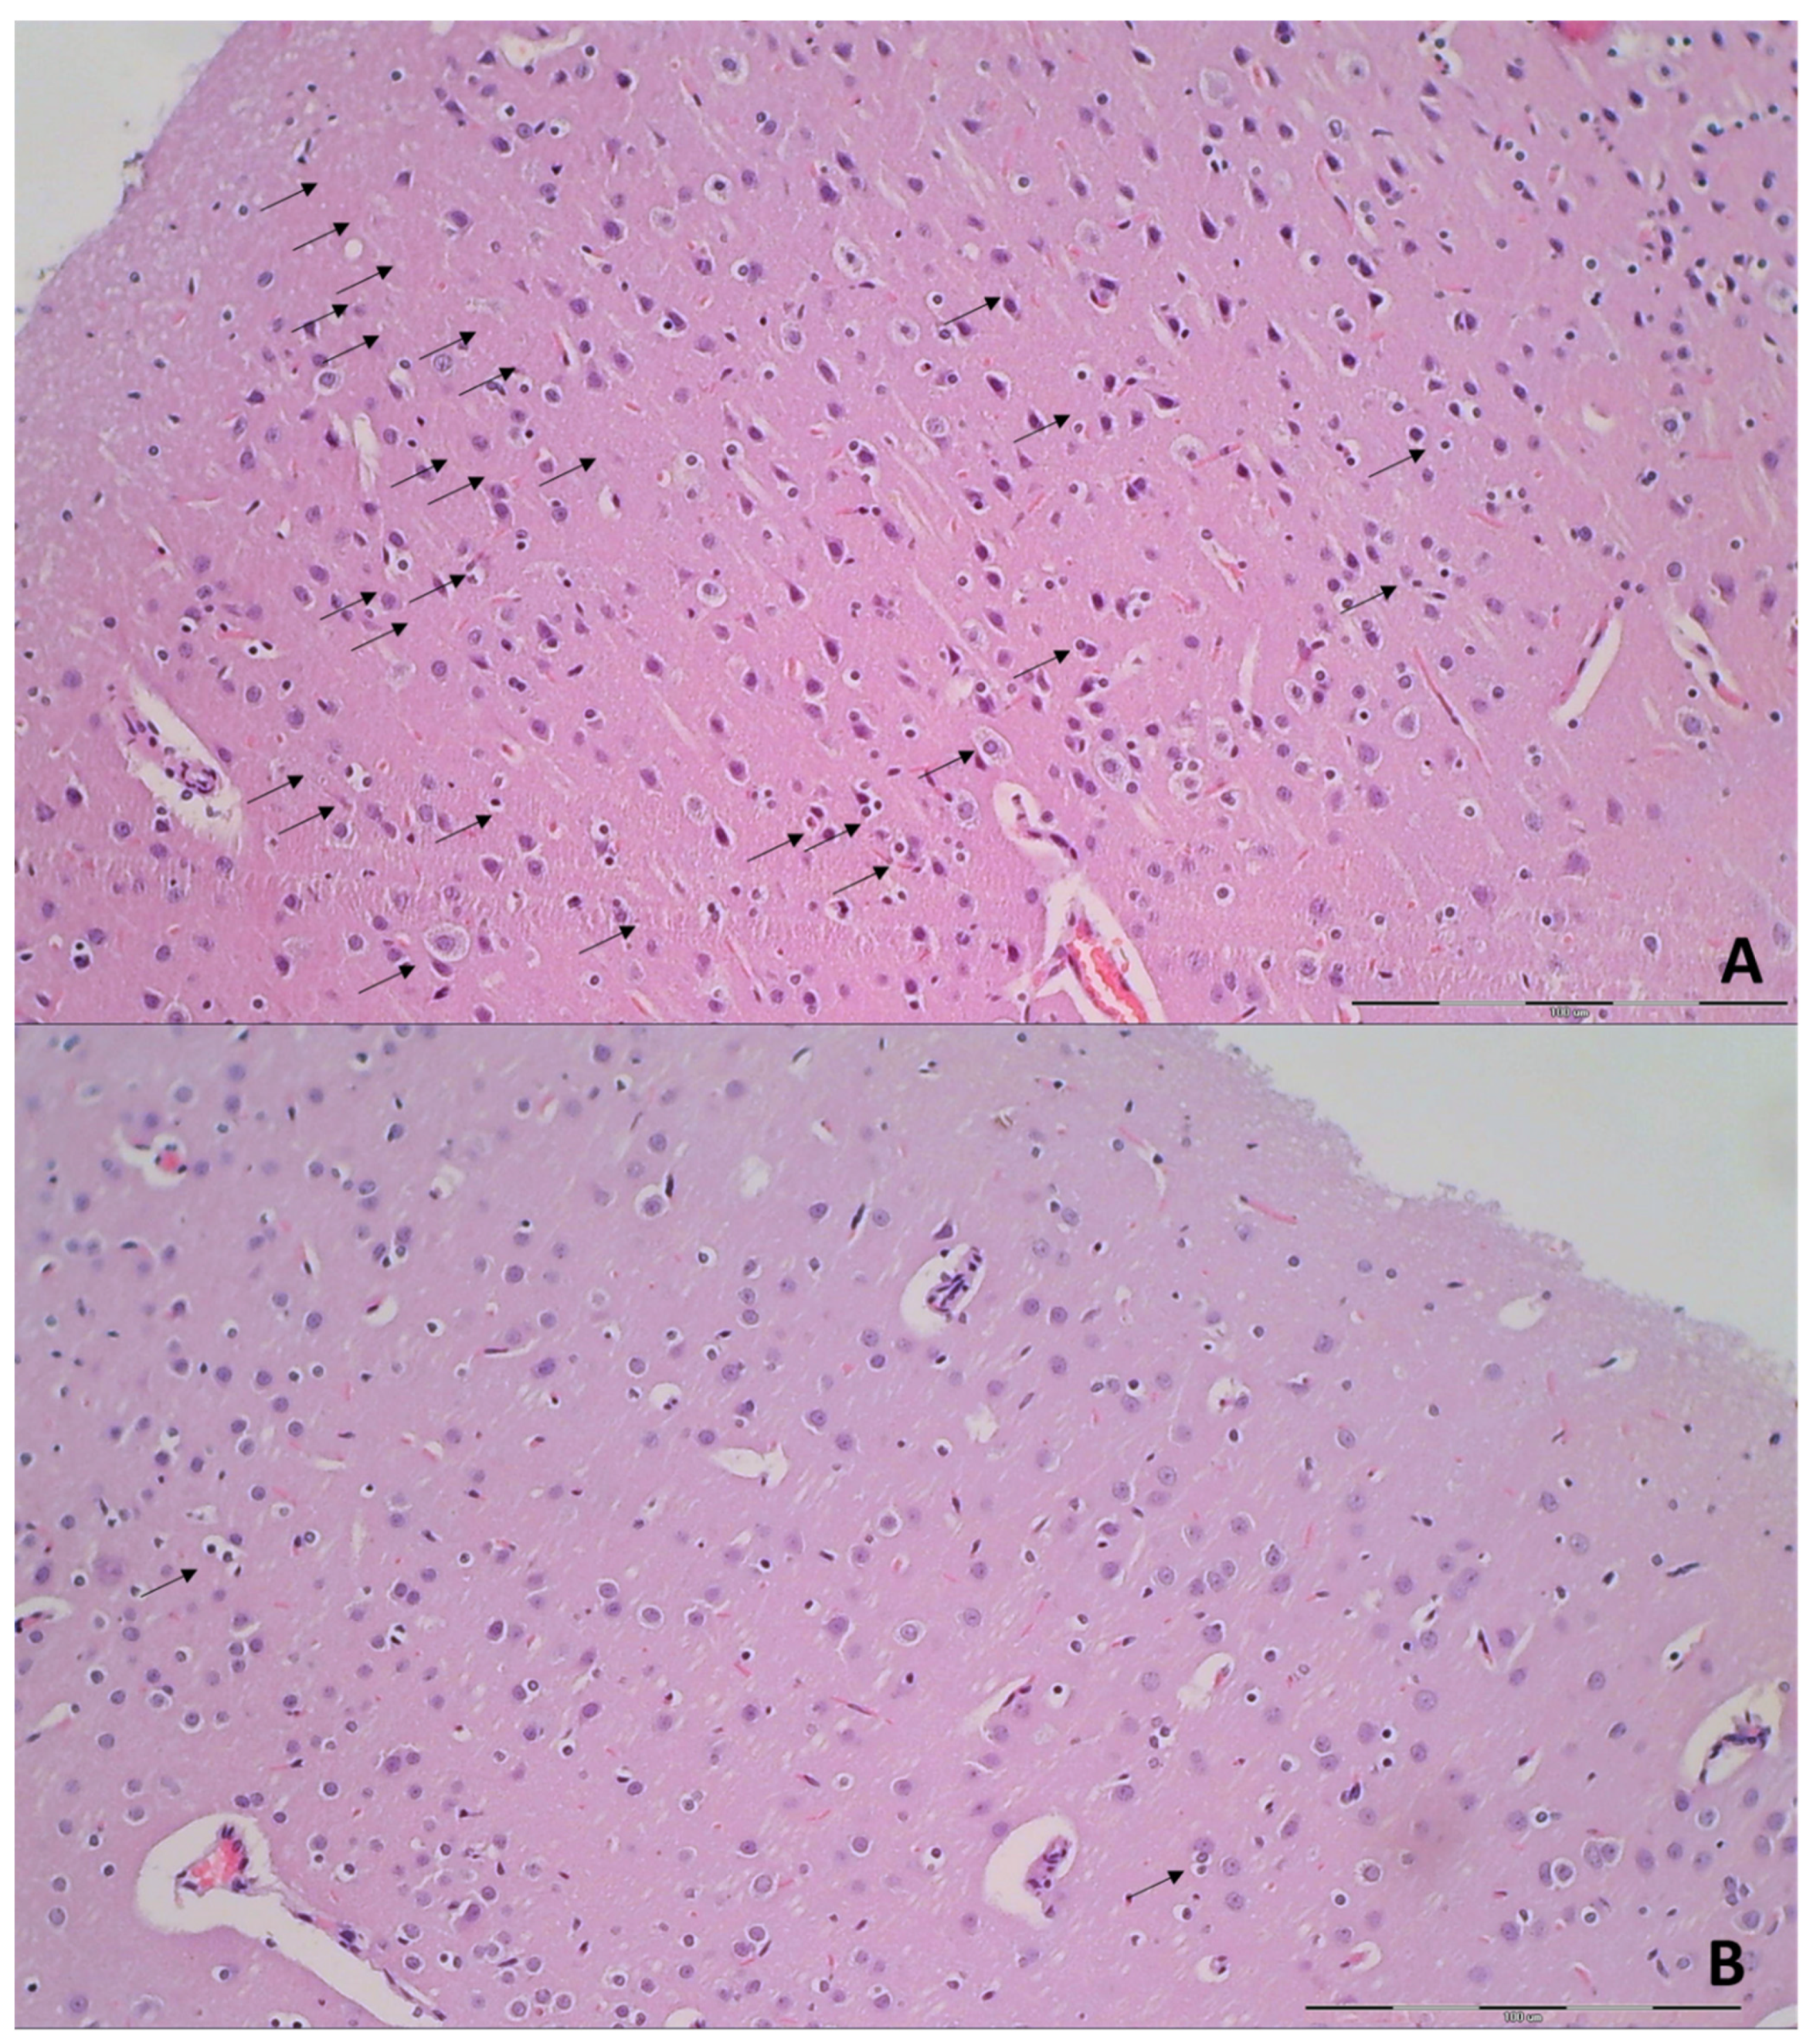

3.9. Histology

| Brain Area | Grading | Percent Area Affected | Morphological Changes |

|---|---|---|---|

| Cerebral and cerebellar cortex, hypothalamus, thalamus, hippocampus | 1 | ≤10 | Small, patchy, complete or incomplete infarcts |

| 2 | 20–30 | Partly confluent complete or incomplete infarcts | |

| 3 | 40–60 | Large confluent compete infarcts | |

| 4 | >75 | In cortex; total disintegration of the tissue, in hypothalamus, thalamus, hippocampus; large complete infarcts | |

| Cerebral and cerebellar cortex, hypothalamus, thalamus, hippocampus | 1 | ≤20 | A few karyopyknotic of neuronal cells |

| 2 | 50 | Patchy areas of karyopyknotic areas | |

| 3 | 75 | More extensive of karyopyknotic areas | |

| 4 | 100 | Complete infarction |